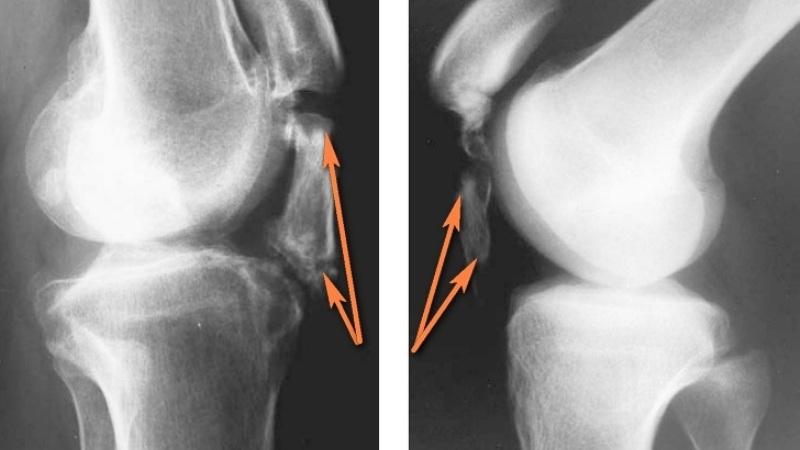

На начальном этапе врач направит вас на ультразвуковое исследование и рентген. Если потребуется, может быть назначено МРТ. Анализируя полученные данные, специалист сможет сделать выводы о характере изменений. На снимках четко видны участки накопления солей и зоны окостенения.